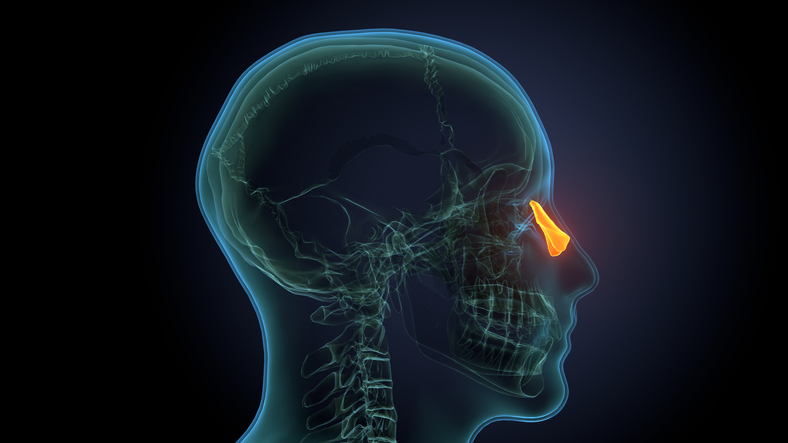

Healing patterns after endodontic treatment for odontogenic maxillary sinusitis

Researchers have explored outcomes across patients with odontogenic maxillary sinusitis who received nonsurgical endodontic therapy.

In a case series published in the Journal of Endodontics, the researchers used cone-beam computed tomography at baseline and at up to 17 months follow-up to analyze the differential radiographic healing patterns of the maxillary sinus mucosa and periapical bone following nonsurgical root canal treatment or retreatment in a group of 10 patients with odontogenic maxillary sinusitis.

Following nonsurgical treatment, the researchers observed resolution of maxillary sinus mucosal lesions — including extensive opacification and sinus floor perforations — to normal physiologic thickness by about three months. However, periapical alveolar bone regeneration was slower, taking between three and 17 months, particularly among patients with bone destruction or periosteal displacement such as periapical osteoperiostitis (appearing as a radiopaque halo sign).

The findings highlighted the utility of early postoperative CBCT in the assessment of treatment response among more anatomically complex cases.